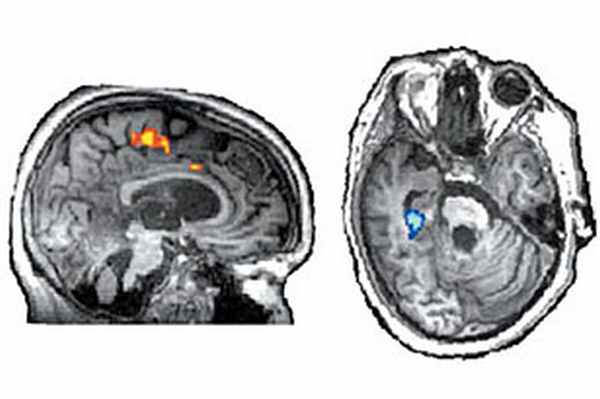

За последние несколько лет исследования вегетативных пациентов с помощью новейших методов магнитно-резонансного сканирования (МРТ) произвели настоящую революцию в неврологии.

Однако, как показали МРТ-исследования мозга, начатые пять лет назад командой нейрофизиологов из Кембриджа (в ее состав входил тогда и Эдриан Оуэн, один из авторов статьи в Lancet),

у части таких больных сознание в той или иной степени сохраняется, что заставило пересмотреть методы и критерии диагностики вегетативных состояний, сплошь да рядом оказавшихся не такими уж и вегетативными.

Теперь в дополнение к дорогостоящей, громоздкой, не всегда доступной и, главное, не всегда возможной в случае таких тяжелых пациентов процедуре МРТ канадская группа предлагает использовать намного более простой и дешевый способ детекции сознания у больных с сильными дисфункциями головного мозга — электроэнцефалографию.

Старую добрую ЭЭГ, дающую, как считается, более общее и примитивное представление о процессах, происходящих в мозге, по сравнению с магниторезонансной томографией, авторы испытали в двух европейских клиниках на 16 пациентах с диагнозом «вегетативное состояние», поставленным в соответствии с принятыми в современной неврологии четкими критериями, отличающими его от коматозного, а также от состояний с «частично сохраняемым сознанием», позволяющим установить с пациентом двустороннее общение.

К удивлению врачей, серия ЭЭГ-тестов, во время которых совершенно безнадежных вегетатиков просили мысленно сжать руку или подвигать ногой, показала, что

примерно каждый пятый такой больной (трое из 16 испытуемых) демонстрировал отчетливые признаки сознания.

В ответ на конкретные просьбы их мозг (точнее, его нейромоторные области, расположенные в коре) проявлял специфичную электрическую активность в μ (7–13 Hz) и β (13–30 Hz) диапазонах. Электрические сигналы снимались с прикрепленных к голове 25 ЭЭГ-датчиков.

По мнению канадской группы, использование ЭЭГ открывает совершенно новые возможности не только при постановке точного диагноза пациентам с тяжелыми поражениями мозга, но и для налаживания двустороннего контакта с тяжелобольными, которых, в согласии со старыми критериями, отнесли бы к «безнадежным вегетатикам».